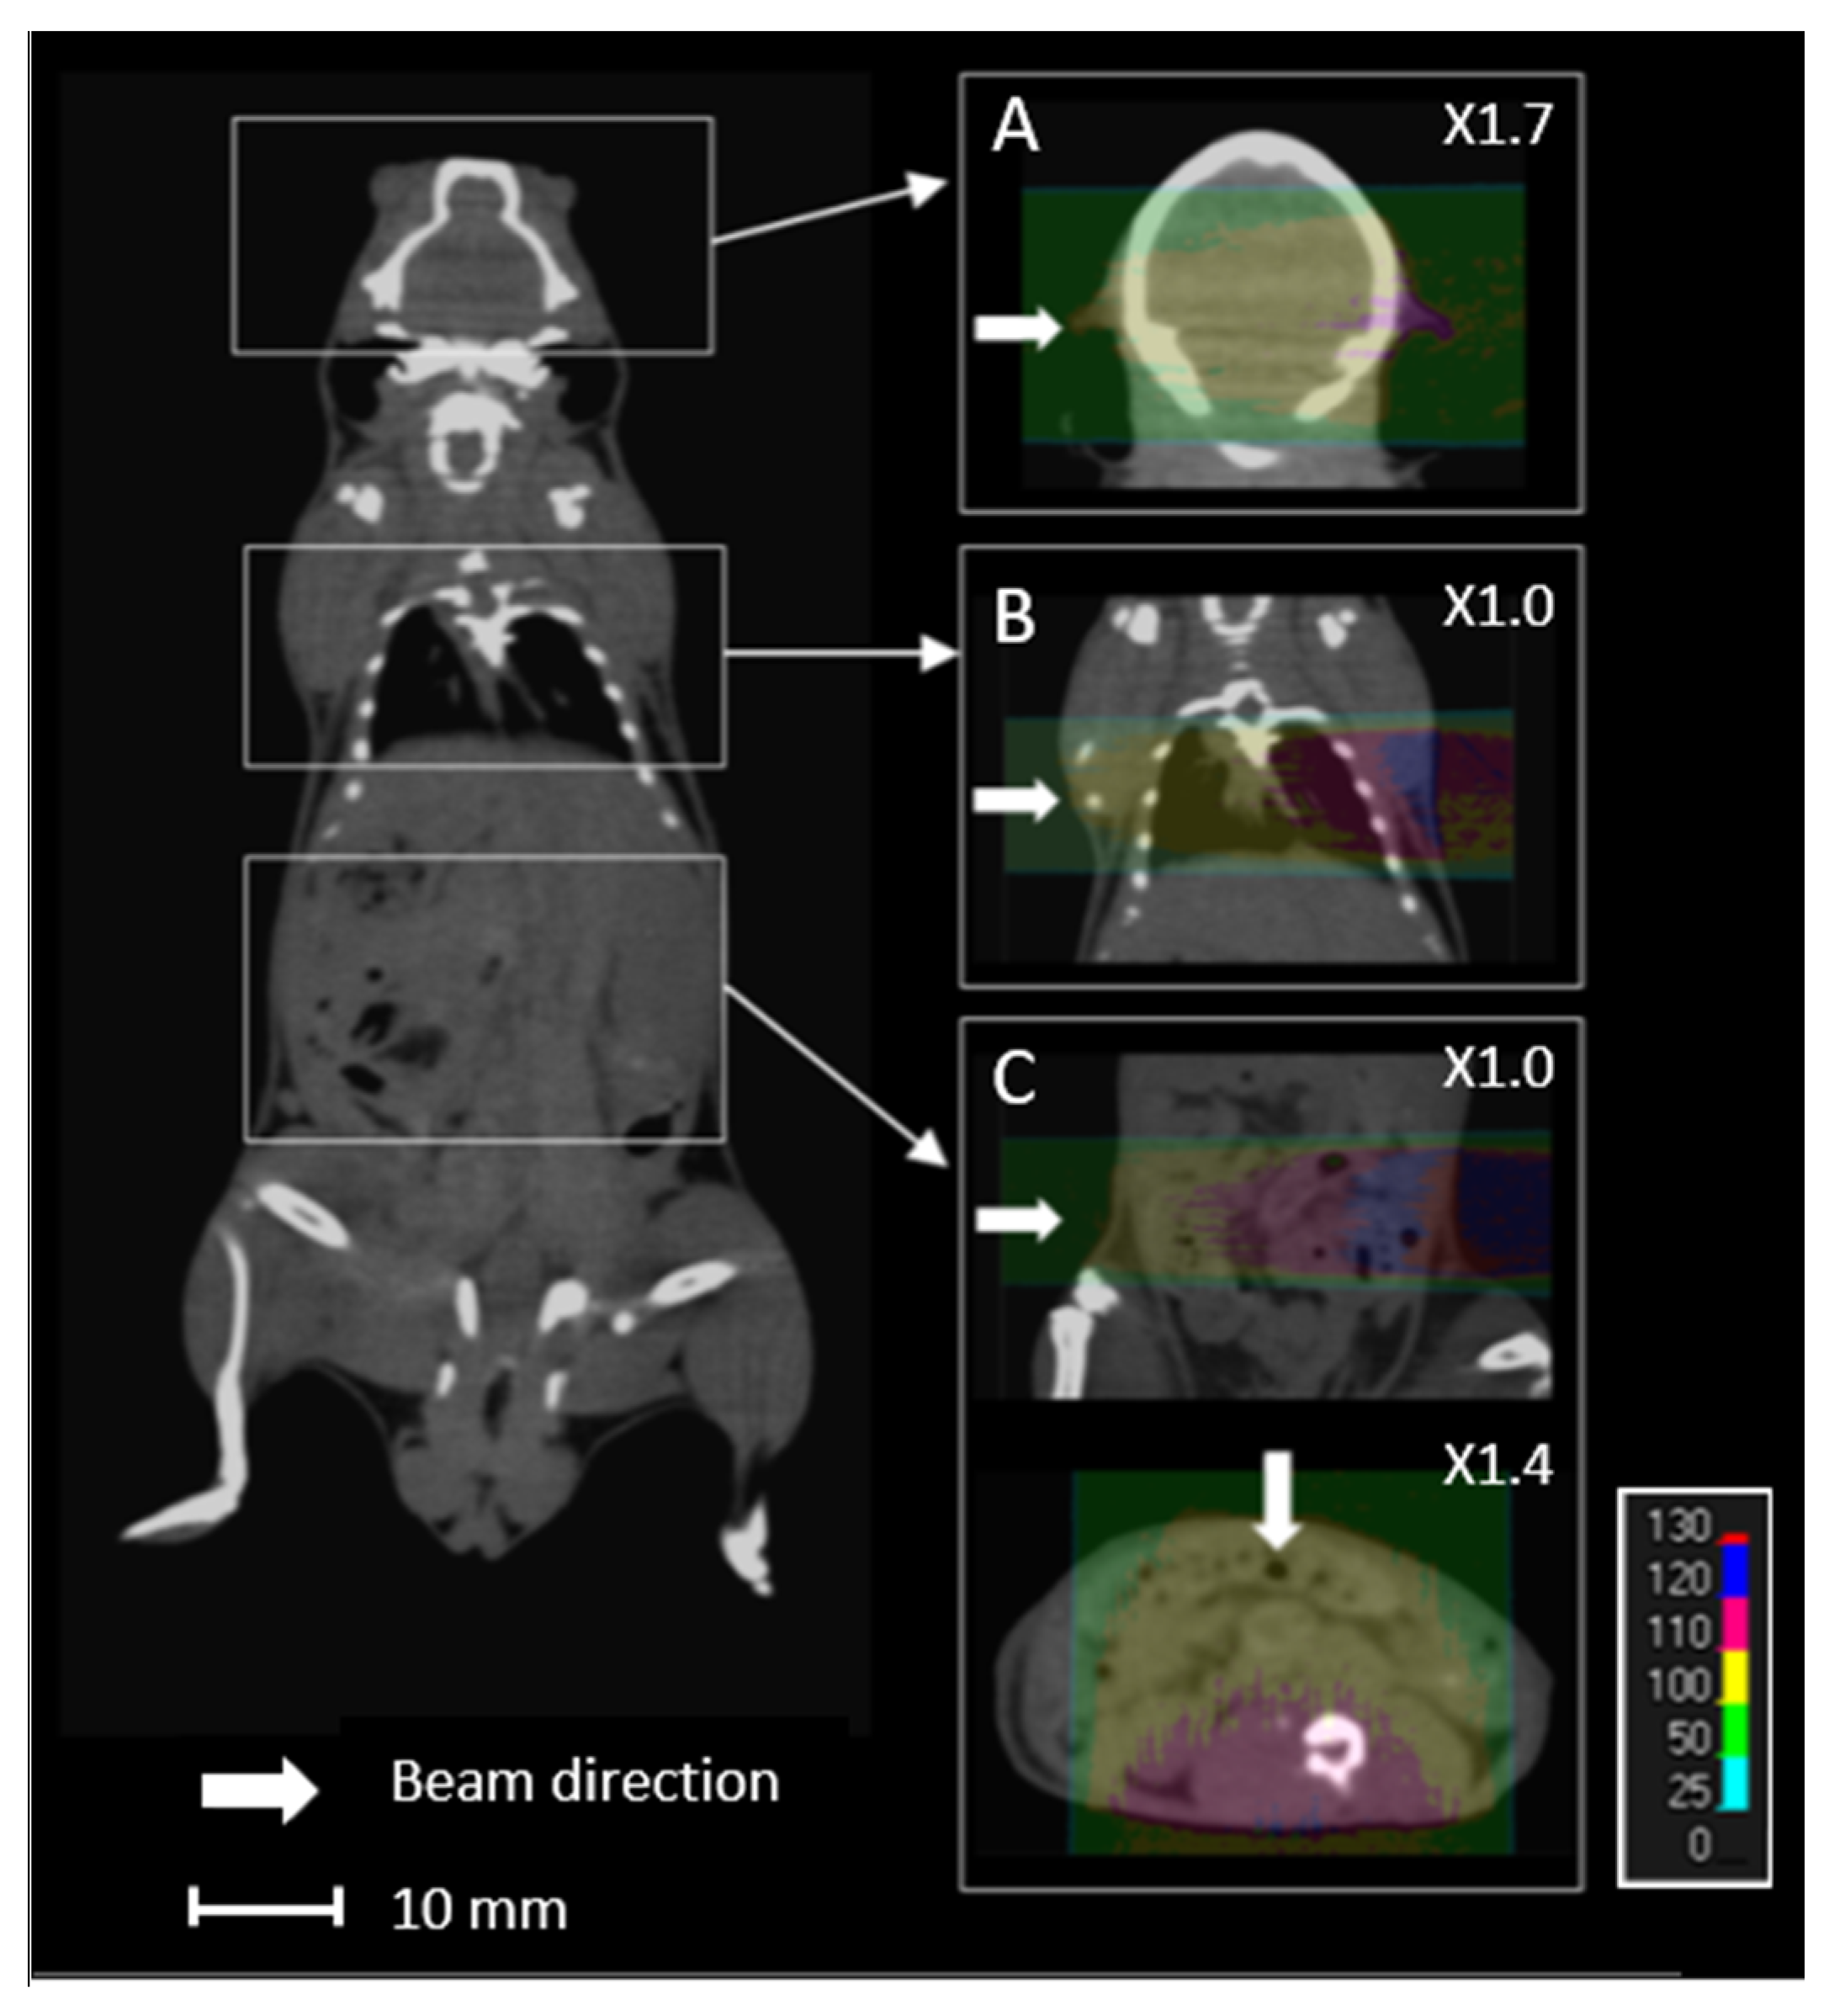

Proton energy (68 MeV, range ≈ 3.5 g/cm2) was adapted for the irradiation of small biological samples, such as cells, zebrafish embryos, or small animals [8]. Examples of dose calculations computed on mouse cone beam computed tomography (CBCT) images for the ARRONAX proton beam are provided for lung, brain, and intestinal irradiation in the Bragg curve (Figure 1). The experimental setup is detailed in Figure 2 and Table 1. The collimator‘s diameter varied from 7 mm to 20 mm. For beam diameters greater or equal to 10 mm, a scatterer (thin tungsten foil) was also added to homogenize the beam with a very small impact on the beam energy. In our study, we simulated two types of targets: the biological sample and the mouse. The biological sample, such as cells or zebrafish embryos, is always placed in liquid during the irradiation. Therefore, it is assimilated to a water cylinder, 4 cm long, along the beam axis.

Figure 1.

Overview of an overlay of a mouse cone beam computed tomography (CBCT) scan and the relative dose (%) obtained from simulated data for 68 MeV proton beam irradiation. Each line (A–C) comprises the simulated data of the brain, lungs, and intestines, respectively, with lateral (A–C) and anterior (C) proton beams.

Lastly, we studied the impact of sources of uncertainty on the dose homogeneity. This is of particular interest for projects related to the limitation of toxicity to normal cells during proton beam irradiation [30,31]. The homogeneity of the target, characterized by the HI98 value, can be difficult at a low energy (68 MeV)—therefore, a short length of the plateau. In the literature, the maximum recommended clinical value of HI98 corresponds to a range of +7% and −5% of the prescribed dose [27]. A tungsten-free configuration allows a water target as thick as 20 mm to be treated with a satisfactory HI98. This thickness can be reduced to 15 mm with a tungsten foil. For small animals, if we consider a lateral beam, the HI98 calculated for the brain and lungs are 0.09 and 0.12, respectively, along the beam axis. These values are comparable to the recommended maximal clinical value of 0.12 [27]. However, this value can reach 0.31 for the intestinal target, due to the large thickness of the abdomen. In this case, it is preferable to irradiate with an anterior beam, which reduces the HI98 to 0.13 (Figure 1). Consequently, using two opposite beams could drastically improve the homogeneity of the dose in the target [32]. More generally, when feasible, the use of several beams with various angles could also reduce the impact of proton range uncertainty.